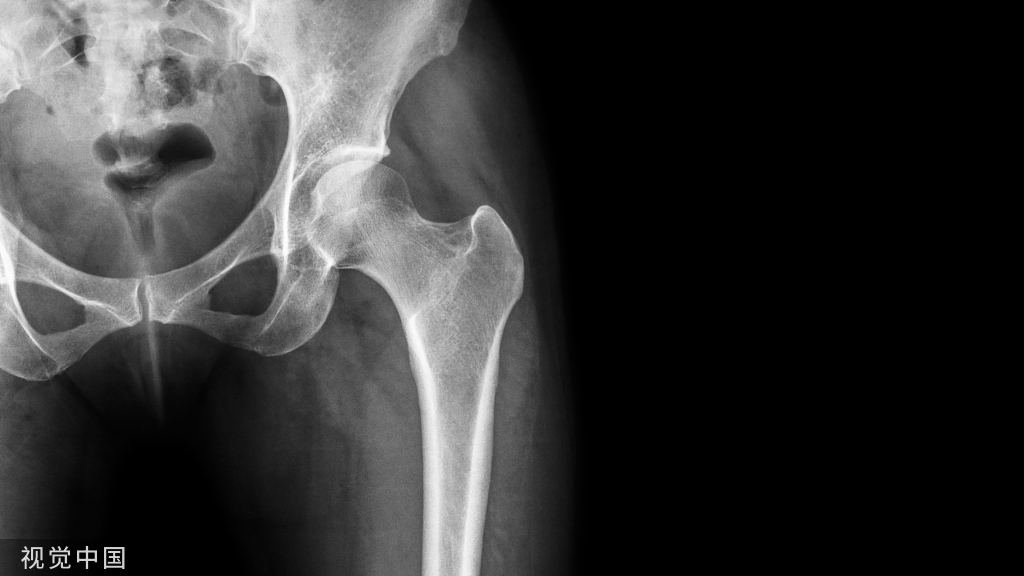

Pauwels Ⅲ型

垂直剪力大,易内翻、固定失败、骨不连

内翻、断钉

股骨颈粉碎骨折(尤其股骨颈后内侧粉碎者)

严重骨质疏松